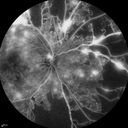

30 y.o man Type I with Red spot then line of yellow like dry blood" os, Started last weekend after nausea from stomach

bug. New floater in the left eye started 4 days ago. VA OD: cc20/20 NccJ1+ OS: cc20/160-1 PH20/100-2 NccJ4. Extensive PDR in both eyes.

Proliferative Diabetic Retinopathy - Moderate - mild NVD with NVE 494 viewsFA shows leakage from neovascularization and dark areas in periphery from non-perfusion     (0 votes)

Proliferative Diabetic Retinopathy - Moderate - mild NVD with NVE 910 viewsFA shows leakage from neovascularization and dark areas in periphery from non-perfusion     (0 votes)